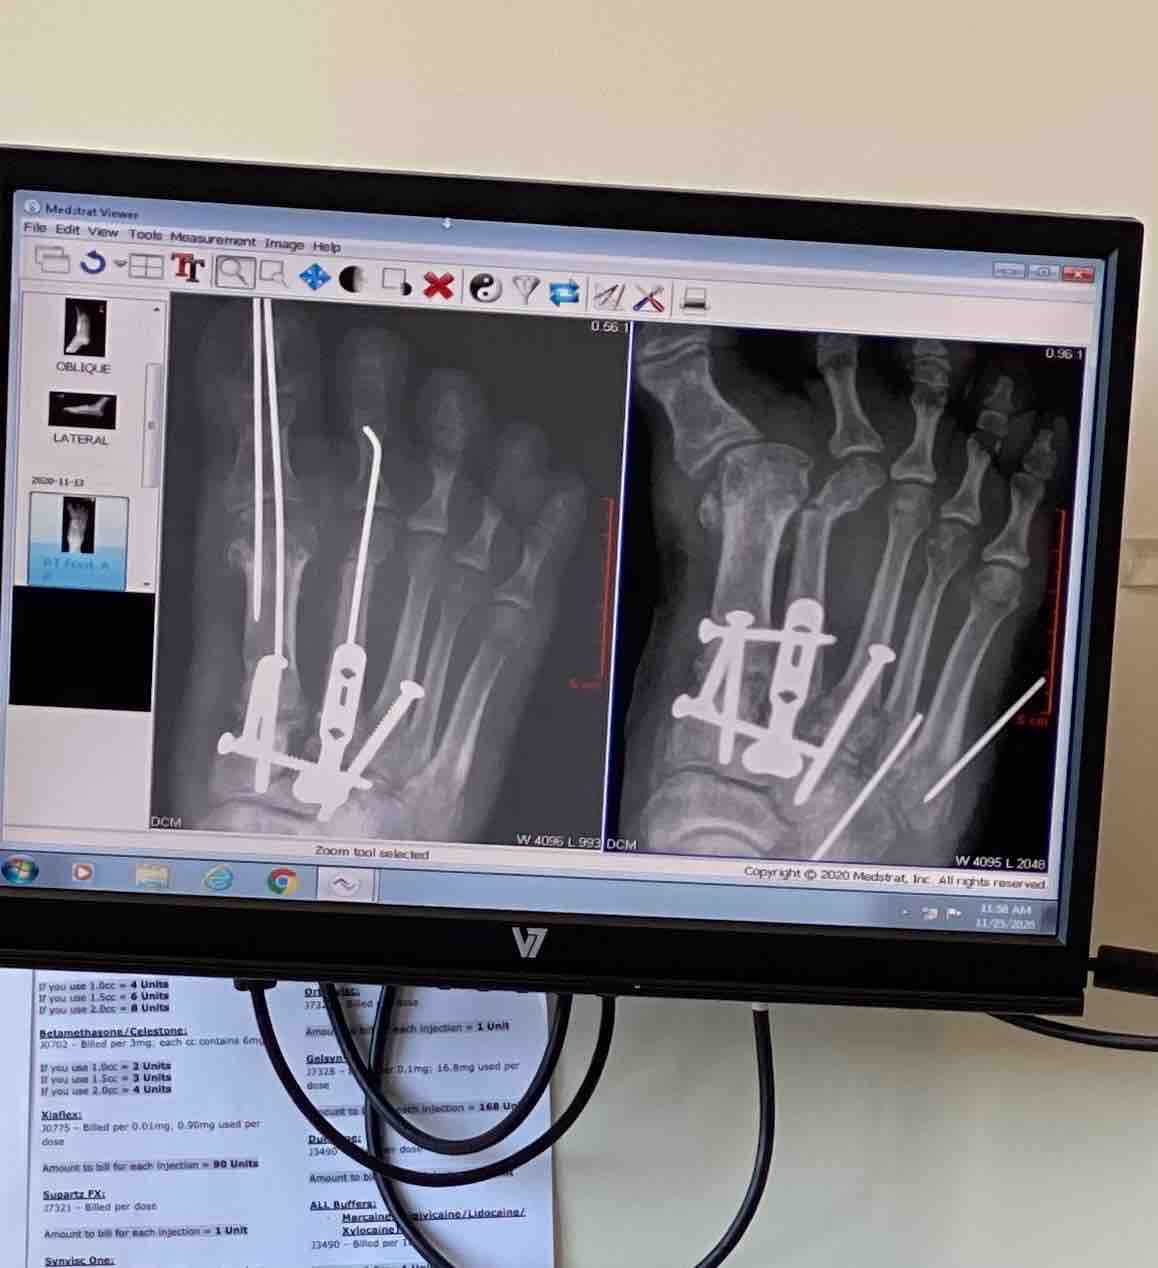

Hi, my name is Kay, and I’m asking for help during one of the hardest chapters of my life. In 2022, I was in a devastating car accident that left me with serious, permanent damage to my spine and a severely deformed foot . Everything changed in an instant. I went from living an independent life to struggling with daily pain, limited mobility, and the reality of rebuilding from the ground up. Despite everything, I refused to give up. Over time, I slowly began putting the pieces of my life back together. I pushed through the pain and fear and started finding purpose again. By June, I was finally able to take a meaningful step forward — I began offering mobile hair care services for the elderly and disabled in my community. Helping others who are homebound like me gave me a sense of purpose and dignity again. I also returned to college, determined to create a better future for myself despite my disabilities. For the first time since my accident, I felt hope. Then, everything changed again. I suffered another fall that severely worsened my already damaged spine. Now, I am facing even greater physical limitations, more intense pain, and the possibility of additional medical procedures, including surgery. On top of that, I have lost my vehicle — which was my only connection to the outside world. Without transportation, I cannot get to my medical appointments, continue my small business, attend school, or even handle basic necessities like grocery shopping. Let’s not forget my animals . My income is below poverty due to lack of work and I am desperately holding on . After I pay my bills I have nothing . I don’t have the money to buy dog food I am completely isolated. I’ve been to every resource but their funding has been dropped unless you are currently homeless which is what I’m trying to avoid . I can’t be homeless w my mobility issues and no car but it’s right around the corner if I don’t ask for help . I currently need to get them food, hire a dog walker and trainer and get my dogs to the vet for flea medication and I can’t even do that without a car or money and I cannot rehome them they are all I have